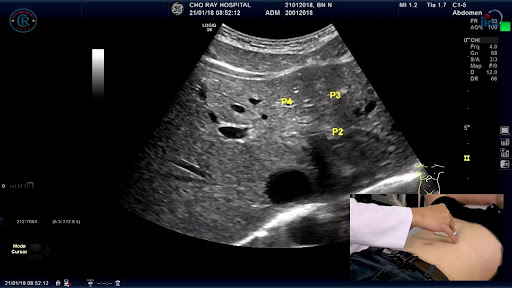

Siêu âm ổ bụng hoặc xét nghiệm là phương pháp chẩn đoán viêm gan hiệu quả.

Bên cạnh xét nghiệm máu, bác sĩ cũng có thể bạn lấy sinh thiết gan hoặc mẫu mô gửi đến phòng thí nghiệm, siêu âm gan để đánh giá mức độ tổn thương gan. Ngay cả khi các dấu hiệu bệnh biến mất, bạn vẫn cần lấy mẫu máu để xác định tình hình xem bệnh của chuyển biến từ cấp tính (nhiễm trong vòng 6 tháng) sang dạng mãn tính (tồn tại hơn 6 tháng) hay không.